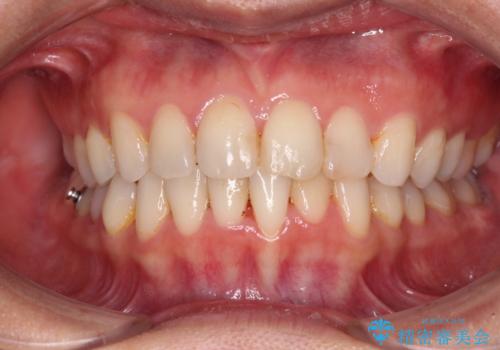

前歯の叢生をいつの間にか改善 インビザラインによる矯正治療

- 前歯のデコボコを気にして来院された患者様です。

IPR(歯と歯の間を削る)によってデコボコが解消するように設計し、インビザラインにより治療を行うこととしました。

下顎善の叢生をもう少し改善したかったのですが、患者様は十分に整ったとのことで治療を終えることになりました。